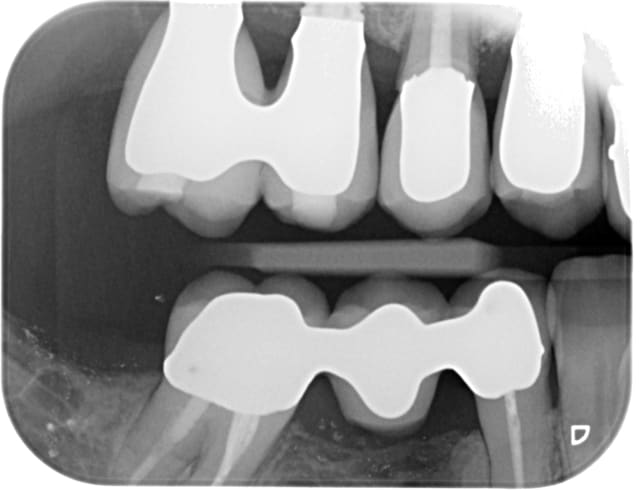

Egalement qu'en est-il de l'ordre de pose des couronnes et bridges? Je sais bien que des implants ne sont pas censés bouger mais si l'on prend le postulat que 15 est prise en sandwich entre 14 et 16 qui basculent vers elle alors on a un effet coin qui enfonce 15 (voir le point de ctct au fil dentaire)

C'est la seule explication qui me semble plausible, d'autant plus que les points de contact étaient réglés assez fort